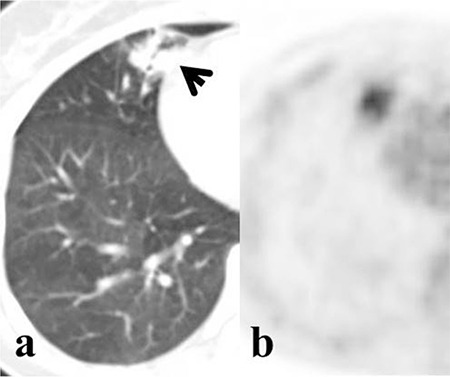

Methods: Tumors were divided into 2 groups according to CT appearance: Group 1: nodular-type tumor; group 2: mass- or pneumonic-type tumor. Unilateral and bilateral multifocal diseases were detected. Clinicopathological characteristics and PET/CT findings were compared between IMAs and LPAs, as well as between survivors and non-survivors.

Conclusions: Although CT images were useful for the differential diagnosis of LPAs and IMAs, SUVmax was not helpful for differentiation of these 2 groups. However, both 18F-FDG uptake and CT findings may play an important role in predicting prognosis in these patients.